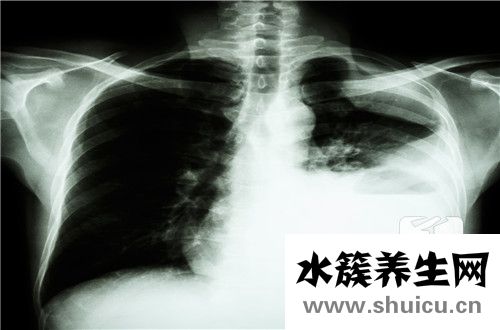

肺健康對人體非常重要,因為肺是呼吸循環(huán)的中心,人必須通過肺才能實現(xiàn)血液輸送氧氣的功能。盡管肺在體內(nèi)占據(jù)了很大的體積,但它們很容易受到疾病的影響,并給人們帶來很多痛苦。例如,肺部炎癥是一種常見...